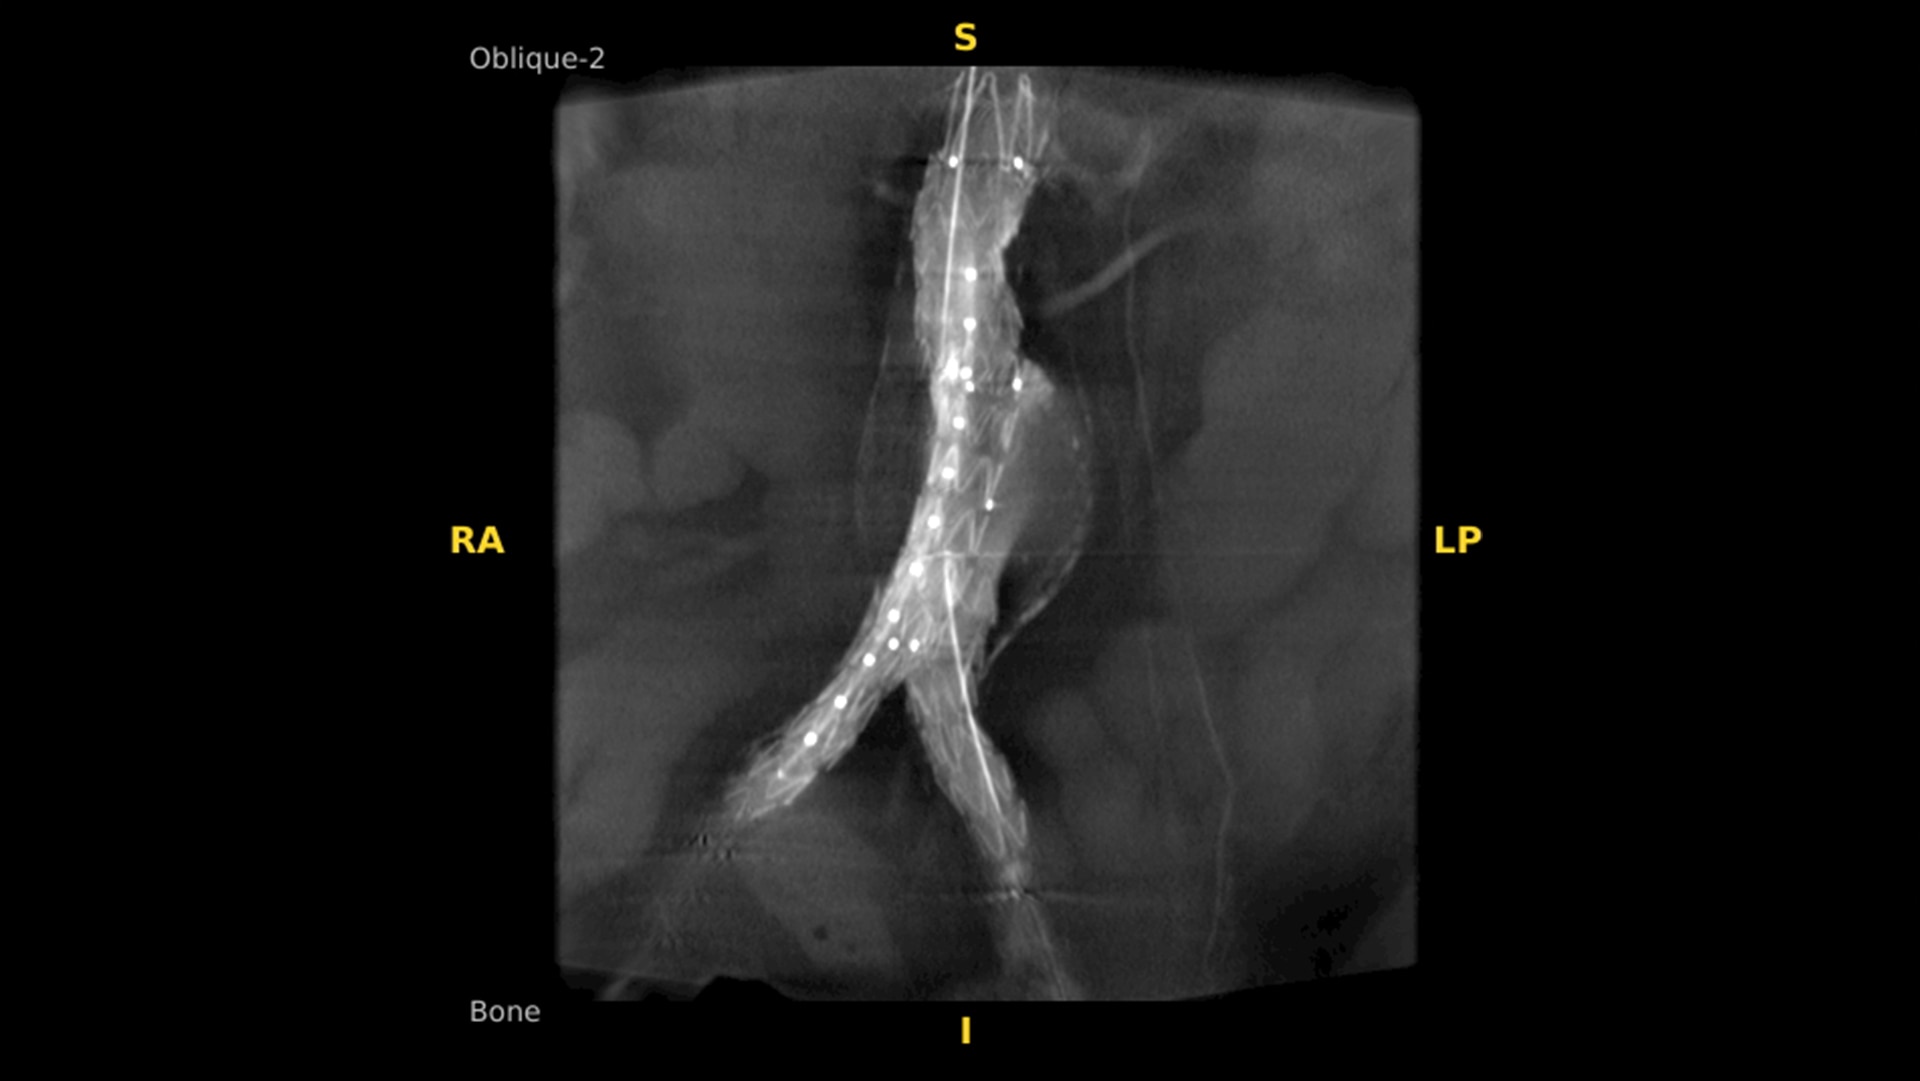

Presents five 3D perspectives and advanced analysis tools, such as Augmented Fluoroscopy overlays

Enhance intraoperative decision-making with visualization capabilities of Augmented Fluoroscopy in the OEC 3D Volume Viewer. Analyze five perspectives with 3D imaging tools including Multi-Oblique Mode, scrolling 512 slices, zoom, and more.